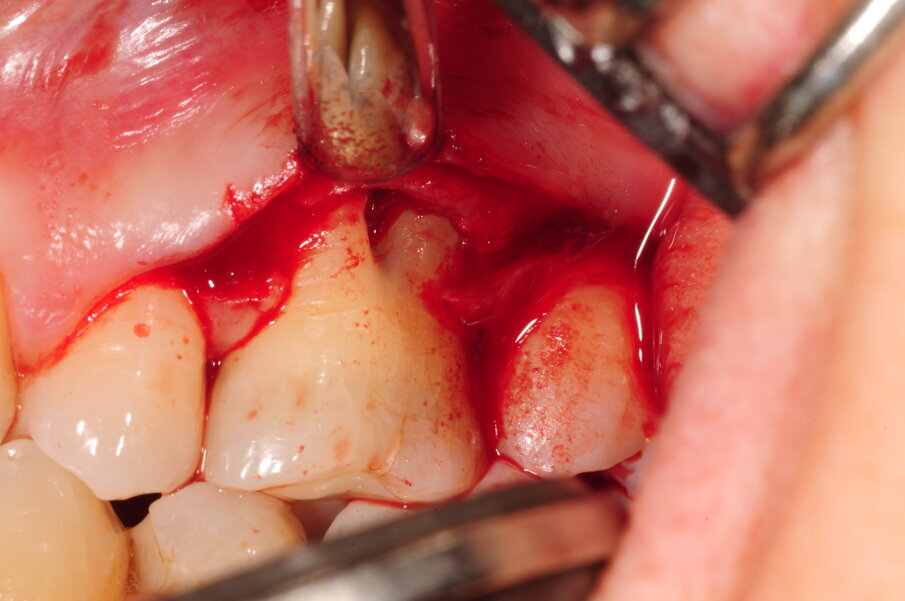

Il Paziente veniva premedicato con Zitromax 500 mg e Ibuprofene 400 mg. Eseguita anestesia loco regionale con articaina 1:100.000 con adrenalina veniva sollevato un lembo muco periosteo a spessore totale con tecnica di preservazione di papilla MPPT (Cortellin i 1995) e incisione intrasulculare (Figg 6d, 6e). Il difetto in sede interprossimale e vestibolare è stato degranulato con ultrasuoni e curette manuale. Raggiunta la perfetta decontaminazione del sito è stata preparata la barriera GUIDOR matrix barrier partendo dalla configurazione specifica per difetti interprossimali (DC double curved) in modo da renderne corretta la dimensione mesio distale e apico coronale (Fig. 6f) .

Fig. 6d - Lembo sollevato con preservazione papille.

Fig. 6e - Difetto infraosseo mesiale.

Fig. 6f - Membraba Guidor in situ.